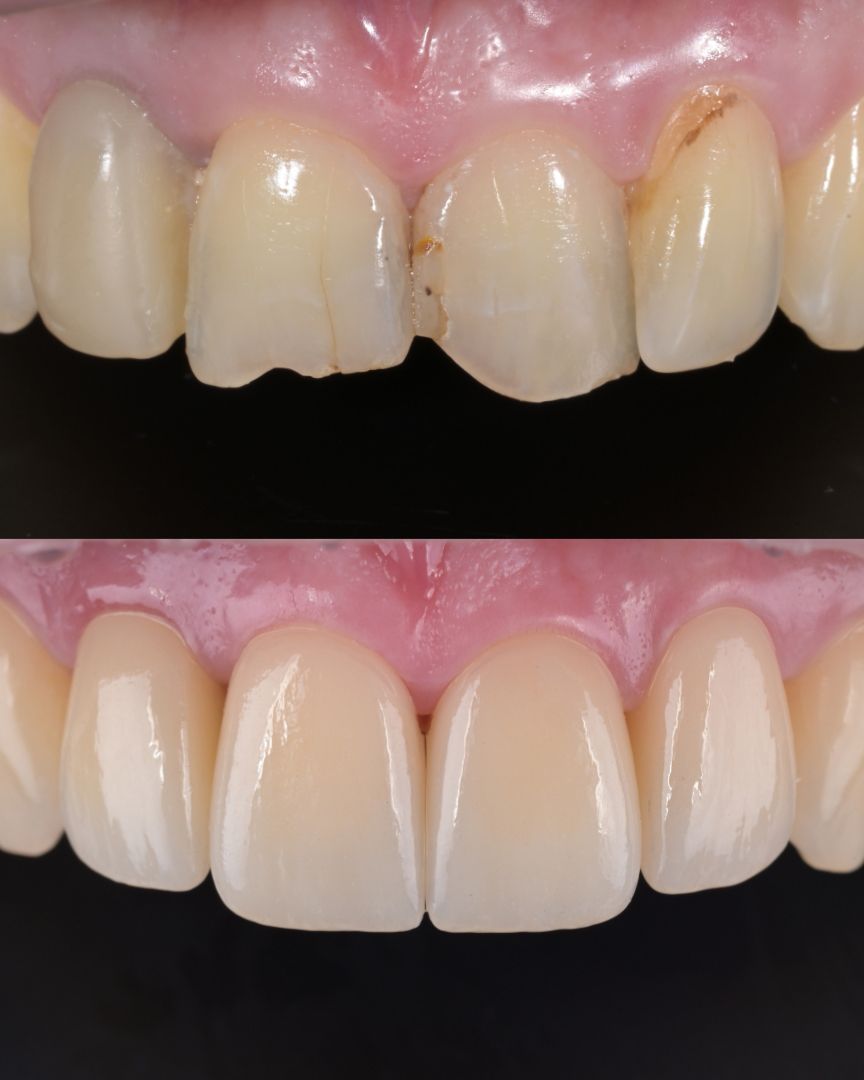

до и после